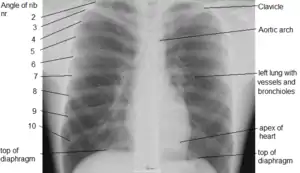

صورة أشعة صدرية ذات جودة عالية.